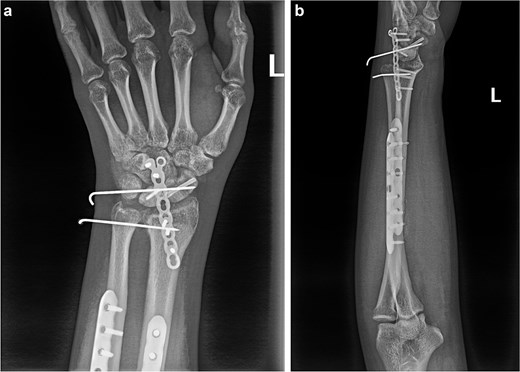

(a and b) After the first operation, X-ray images revealed that the volar displaced scaphoid fracture end had been incorrectly fixed to triquetrum fracture end. Temporary fixation of the unstable wrist joint was achieved using Kirschner wires, while the ulna and radius were not fixed. The lunate bone had not yet been completely repositioned.